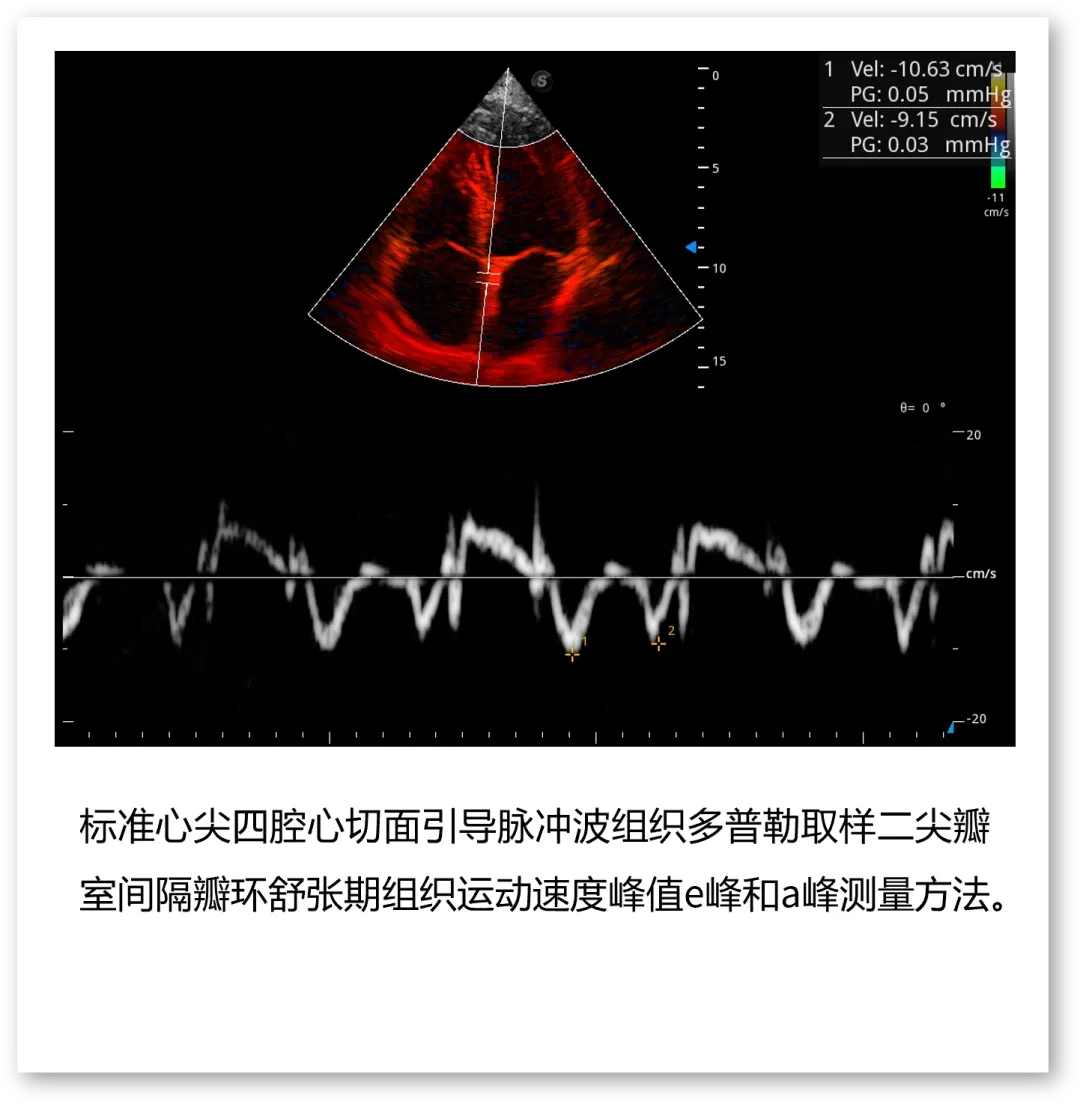

开立医疗联合武汉大学中南医院心血管病医院,将《心脏超声检查规范化中国专家共识 (2024版)》内容与实际临床工作需求融合,精心制作了指南挂图,助力标准采集,规范测量,期待这份实用且高清的工具,能成科室提升超声质效的助手!